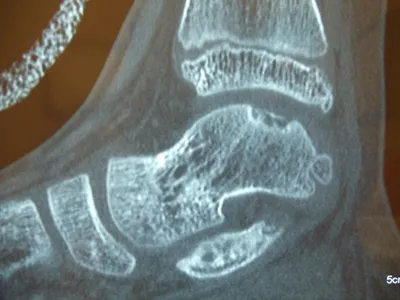

Series of Pics of Microfracture of large OCD of the Talar Dome

Pic of OCD after preparation and debridement .